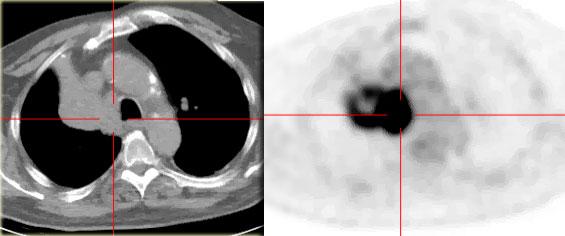

Xẹp thùy trên phổi phải

Hãy quan sát kỹ các hình ảnh trước, sau đó tiếp tục đọc.

Các dấu hiệu:

- Đám mờ hình tam giác

- Rốn phổi phải nâng cao

- Xóa mờ khoang sáng sau xương ức (mũi tên)

Trên PET-CT ghi nhận một khối u phổi kèm theo xẹp thùy trên phổi phải do tắc nghẽn phế quản thùy trên.

Một dấu hiệu thường gặp trong xẹp thùy trên phổi phải là hiện tượng ‘lều hóa’ cơ hoành (mũi tên xanh dương).

Bệnh nhân này có ung thư phổi vị trí trung tâm kèm di căn ở cả hai phổi (mũi tên đỏ).